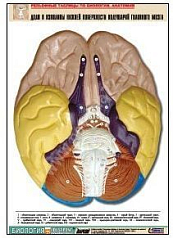

Комплект включает в себя 21 таблицу следующего содержания:

1. Железы внутренней секреции;

2. Доли полушарий головного мозга;

3. Доли и извилины нижней поверхности полушарий головного мозга;

4. Сагиттальные разрез головы;

5. Строение спинного мозга;

6. Глаз. Строение;

7. Ухо человека;

8. Пищеварительный тракт;

9. Челюсти и зубы человека;

10. Желудок. Внешняя и внутренняя поверхность;

11. Ворсинка кишечная с сосудом;

12. Печень. Висцеральная поверхность;

13. Долька печени. Макро-микростроение;

14. Строение легких;

15. Мочевыделительная система;

16. Почка. Фронтальный разрез;

17. Почка. Макро-микростроение;

18. Кожа. Разрез;

19. Строение сердца;

20. Расположение органов грудной и брюшной полостей по отношению к скелету;

21. Таз мужской и женский.

Изделие соответствует Перечню средств обучения и воспитания, утвержденному Приказом Минобрнауки России N 804 (подраздел «Демонстрационные учебно-наглядные пособия для профильного медико-биологического класса»).